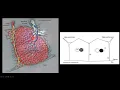

pensamento é tão grande que obter a luz dos alvéolos então você vai ver um a consolidação ok doenças que têm acometimento dos vasos linfáticos vão a cometer predominantemente portanto aqui os septos inter lobulares doenças com acometimento de veias vão cometer predominantemente os septos enterrou populares doenças com o cometimento de arteríolas e bronquíolos e ou de brum quilos vó cometi preferencialmente a região centro lobular ok acho que você já entendeu o raciocínio e já percebeu que é fundamental conhecer bem logo pulmonar secundário e seus componentes temos aqui esse desenho muito ilustrativo temos um certo intervalo goulart

a superfície da pleura outro septo inter lobular delimitando aqui um logo pulmonar secundário no septo interrogar tem veia ele é enfático no meio no centro do lóbulo pulmonar secundário têm bom quilo e arteiro lula foi enfático também vem no festival século brônquico só que eles se ramifica nos septos inter lobulares ele não tem enfático na parede dos alvéolos aqui tem um interstício intra lobular que é uma rede finíssima de tecido conjuntivo que forma que sustenta a parede dos alvéolos tem a rede capilar e vendendo balas na parede dos alvéolos e você tem os espaços auveolares

nesse esquema mais simplificado ainda não tenha se você tem a superfície superior ao dos septos inter lobulares no centro do lóbulo artéria pulmonar ou material no pulmão na e umbro quilo só que o branquinho gente não vai identificar ele na tomografia a gente vai identificar bem a área teria lula na tomografia de um pulmão normal arteríolas entre globular ea gente vai identificar bem essas veias que ficam no campo na junção das linhas cep tais e vamos identificar parcialmente uma outra linha septal mas vai dar para ter uma idéia da composição lobular do pulmão veja aqui

veja o desenho lobos pulmonares secundários veias interlub inter lobulares arteríolas entre lobular com brum quilo excepto sinter lobulares e aqui uma tomografia de alta resolução do tórax do pulmão normal lembra que tem que ser tomografia de alta resolução cortes finos de um milímetro para baixo com um filtro duro que geralmente filtro de osso e janela de pulmão e você vê aqui um século inteiro lobular e uma veia inter lobular exatamente como aqui veja septo e veio você vê aqui um septo em uma veia esses outros pontinhos podem ser v e as menores também mas um

septo um outro septo esboço de um certo e aqui um arteríolas entre o novo lar uma outra teria centro lobular mais um mais um mais outra e mais outra mais outra você não vê o branco quilo adjacente mas tem e então aqui você delimitam logullo pulmonar secundário outro logullo pulmonar secundário mais um golo pulmonar secundário mais um aqui mas outro aqui veja que esse aqui você não consegue saber exatamente o limite então pulmão normal o que você vê isso você até consegue de limitar parcialmente os lóbulos pulmonares secundários você até consegue ver um septo inter

lobular um aqui outro acolá um pedacinho aqui um pedacinho lá é um outro aqui imaginando mais um pouco de imaginação tem um segmento aqui mas você não não consegue imitar perfeitamente os polígonos né as imagens fechadas dono do lóbulo pulmonar secundário isso é o normal veja aqui uma tomografia de alta resolução do pulmão normal você vê um cep inter logo lar aqui arteríolas entre globo lá aqui ou seja não vê um arteríolas entre lobular aqui um septo inter lá um outro aqui um outro ali ok então você já começa a imaginar aí um logo do

pulmonar secundária que outra que outra que certos inter lobulares veja que um lóbulo pulmonar secundário aqui anterior o centro goulart septos inter lobular excepto em triangular aqui aqui aqui e aqui isso tudo normal veja cep enterrou bullard de lula centro lobular um esboço de septo aqui e assim por diante veja aqui esboços de septo sinter lobulares septos interrogo lares parcialmente visualizados aqui também aqui então isso é o normal é o que a gente consegue ver em condições normais agora vamos ver a correspondência disso na histologia temos aqui um corte histológica uma lâmina de pulmão aqui